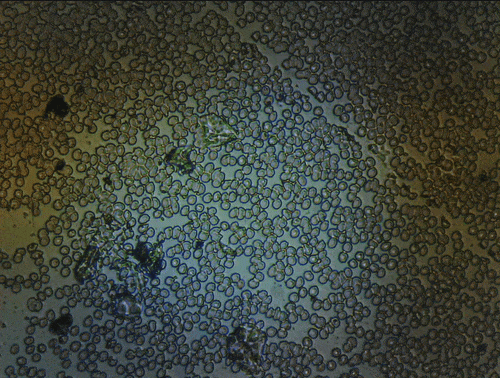

Scanning of red blood cells contaminated with malaria in the field

Stage in Action in continous mode